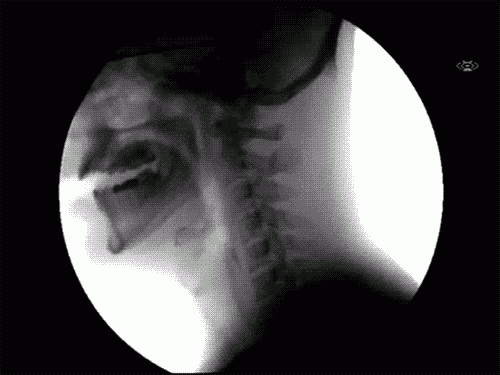

تصوير عملية البلع بأشعة أكس. تحتاج متصفحا حديثا وجافاسكريبت مفعلة لمشاهدة هذا المقطع تحميل الصورة رابط الصورة